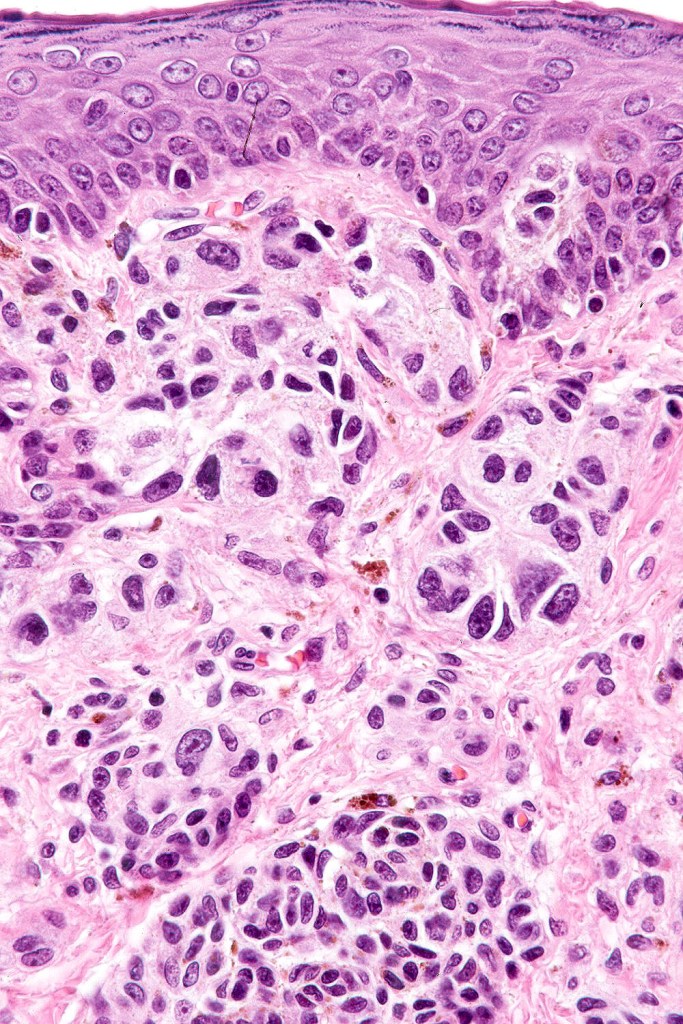

•Characterized by large abnormally distributed junctional nests

•Pagetoid spread (can mimic superficial spreading melanoma)

•Atypical dermal component

•Junctional & dermal mitotic activity

•Impaired or absent maturation

This melanoma arose in a small congenital nevus of the scalp. It metastasized widely. Varying features in different fields.